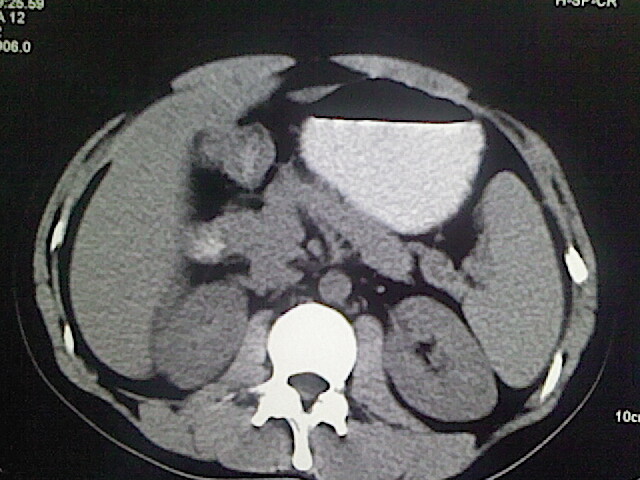

以下是引用卜一在2009-3-14 9:49:00的发言:[br]胆囊萎缩,胆囊壁不规则增厚,内部结构模糊,增强明显强化。另:肝左叶外侧段肝囊肿。支持:慢性胆囊炎!高度可疑:胆囊癌!

以下是引用余辉在2009-3-14 8:48:00的发言:[br]1)慢性胆囊炎。2)肝左叶外侧段肝囊肿。3)脂肪肝。[br]支持,胆囊萎缩,密度增高,不知b超具体有何提示,钙胆汁?结石?

以下是引用jiangjing在2009-3-14 10:18:00的发言:[br]1)慢性胆囊炎。2)肝左叶外侧段肝囊肿。3)脂肪肝。4.】建议行肝功能检查